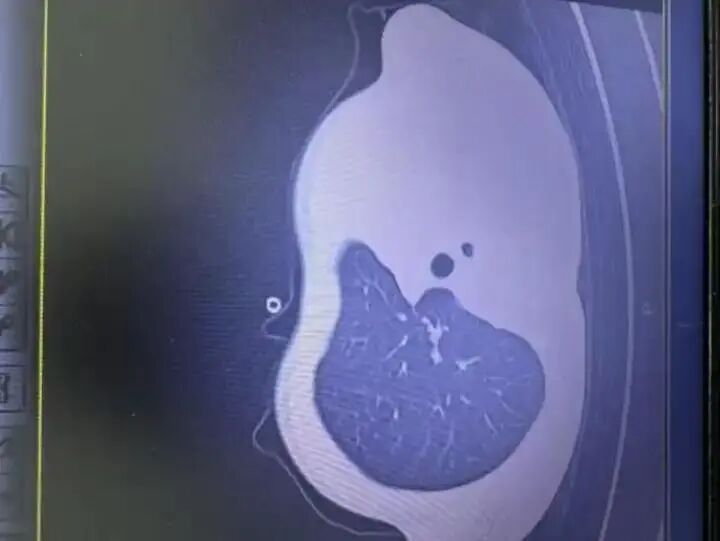

2日早上,小宇出现呼吸急促、嘴唇发紫、精神不振,家人急忙将他送到浙江大学医学院附属儿童医院急诊,胸片检查发现左肺已变“白肺”,随时有窒息危险。由于病情凶险,小宇被紧急送进PICU(儿科重症监护病房)。在气管镜下,医生发现小宇的气道里堵满了树枝状的“痰栓”,呼吸通道完全被塞住,气道内壁还有坏死组织。在ICU的10天里,小宇先后做了5次气管镜,重复冲洗、清理新形成的“痰栓”和坏死组织,同时进行抗感染、抗炎等治疗。直到12月12日小宇才转入普通病房,目前恢复良好。

某些病毒性肺炎在感染初期表现温和,但病程却异常迅猛。尤其在免疫反应过度或病毒复制速度极快的情况下,肺泡渗出液体和炎症细胞,迅速填满肺部。这时候,CT片上就会出现大片白色阴影,也就是“白肺”。

“白肺”并不等于绝症,也不是一种确定的疾病名称。它其实是影像学上的描述,指的是肺部大片实变或渗出,让原本黑色的空气区变成了白色。这种表现常见于严重肺炎、ARDS(急性呼吸窘迫综合征)等病症。